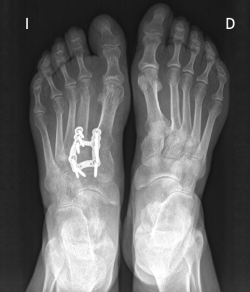

Figura 1. Artrosis primaria de la primera articulación cuneometatarsiana.

Figura 2. Tratamiento quirúrgico mediante artrodesis con placa en proyección dorsoplantar.

Existen distintas opciones de osteosíntesis con tornillos y/o placas. Actualmente, disponemos de diferentes diseños de placas: placas de tipo “Pi” que fijan CMM1-CMM2, placas plantares, mediales, medioplantares o dorsales. Recomendamos el empleo de placas “Pi” si es preciso artrodesar CM-M2 y el uso de placas medioplantares o plantares para la artrodesis aislada de CM-M1, que desde el punto de vista biomecánico son más apropiadas (Figuras 1 a 3). Otro tema de debate es el empleo de injerto óseo esponjoso autólogo o de sustitutivos óseos como la matriz ósea desmineralizada o trifosfatos cálcicos. Recomendamos, especialmente en pacientes menores de 50 años, el empleo de injerto autólogo de cresta ilíaca.